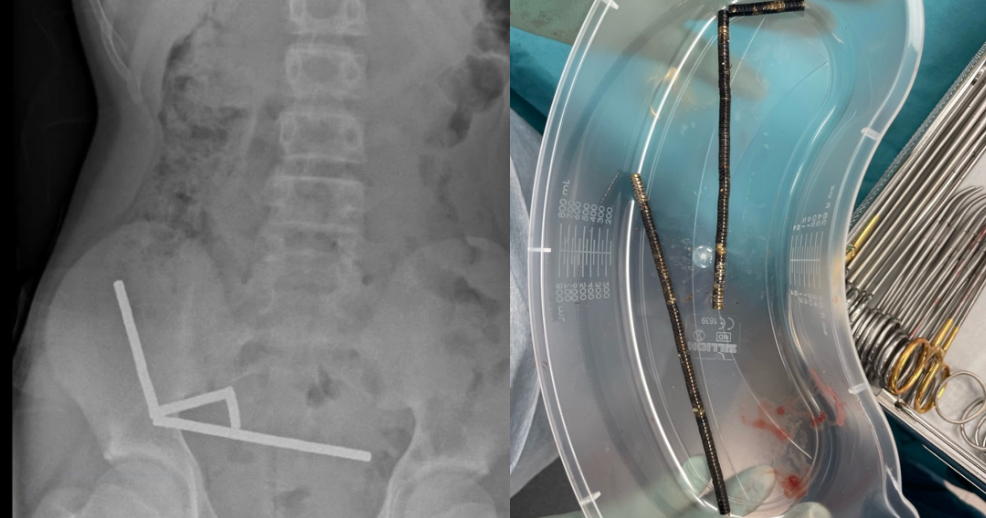

A 13-year-old boy was hospitalized after eating dozens of high-powered magnets, according to a recently published case report in the New Zealand Medical Journal. The boy lost part of his bowel as a result, doctors wrote.